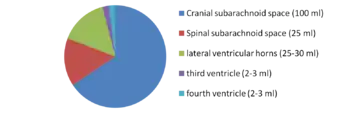

CSF is produced by specialised ependymal cells in the choroid plexus of the ventricles of the brain, and absorbed in the arachnoid granulations. There is about 125 mL of CSF at any one time, and about 500 mL is generated every day. CSF acts as a shock absorber, cushion or buffer, providing basic mechanical and immunological protection to the brain inside the skull. CSF also serves a vital function in the cerebral autoregulation of cerebral blood flow.

There is about 125–150 mL of CSF at any one time.[1] This CSF circulates within the ventricular system of the brain. The ventricles are a series of cavities filled with CSF. The majority of CSF is produced from within the two lateral ventricles. From here, CSF passes through the interventricular foramina to the third ventricle, then the cerebral aqueduct to the fourth ventricle. From the fourth ventricle, the fluid passes into the subarachnoid space through four openings – the central canal of the spinal cord, the median aperture, and the two lateral apertures.[1] CSF is present within the subarachnoid space, which covers the brain and spinal cord, and stretches below the end of the spinal cord to the sacrum.[1][2] There is a connection from the subarachnoid space to the bony labyrinth of the inner ear making the cerebrospinal fluid continuous with the perilymph in 93% of people.[3]

The brain produces roughly 500 mL of cerebrospinal fluid per day at a rate of about 20 mL an hour.[17] This transcellular fluid is constantly reabsorbed, so that only 125–150 mL is present at any one time.[1]